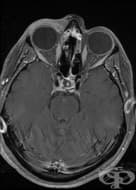

Ядрено-магнитният резонанс на синусите (магнитен резонанс на синусите, ЯМР на синусите) представлява...